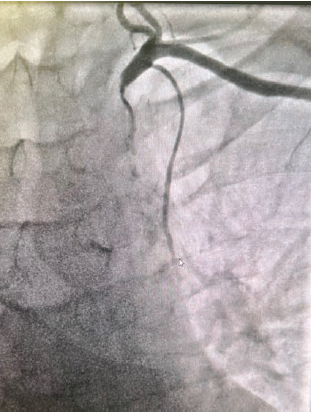

Coronary anatomy revealed a normal left main and an occlusion in the ostial left anterior descending (LAD) at 95%, proximal LAD 70%, mid-LAD 90%, mid left circumflex (LCx) 85%, obtuse marginal (OM)1 70%, OM2 40%, 1st left posterolateral artery 70%, ostial left posterior descending artery 90%, and a right coronary artery (RCA) 100% chronic total occlusion (CTO) (Figures 2-4).